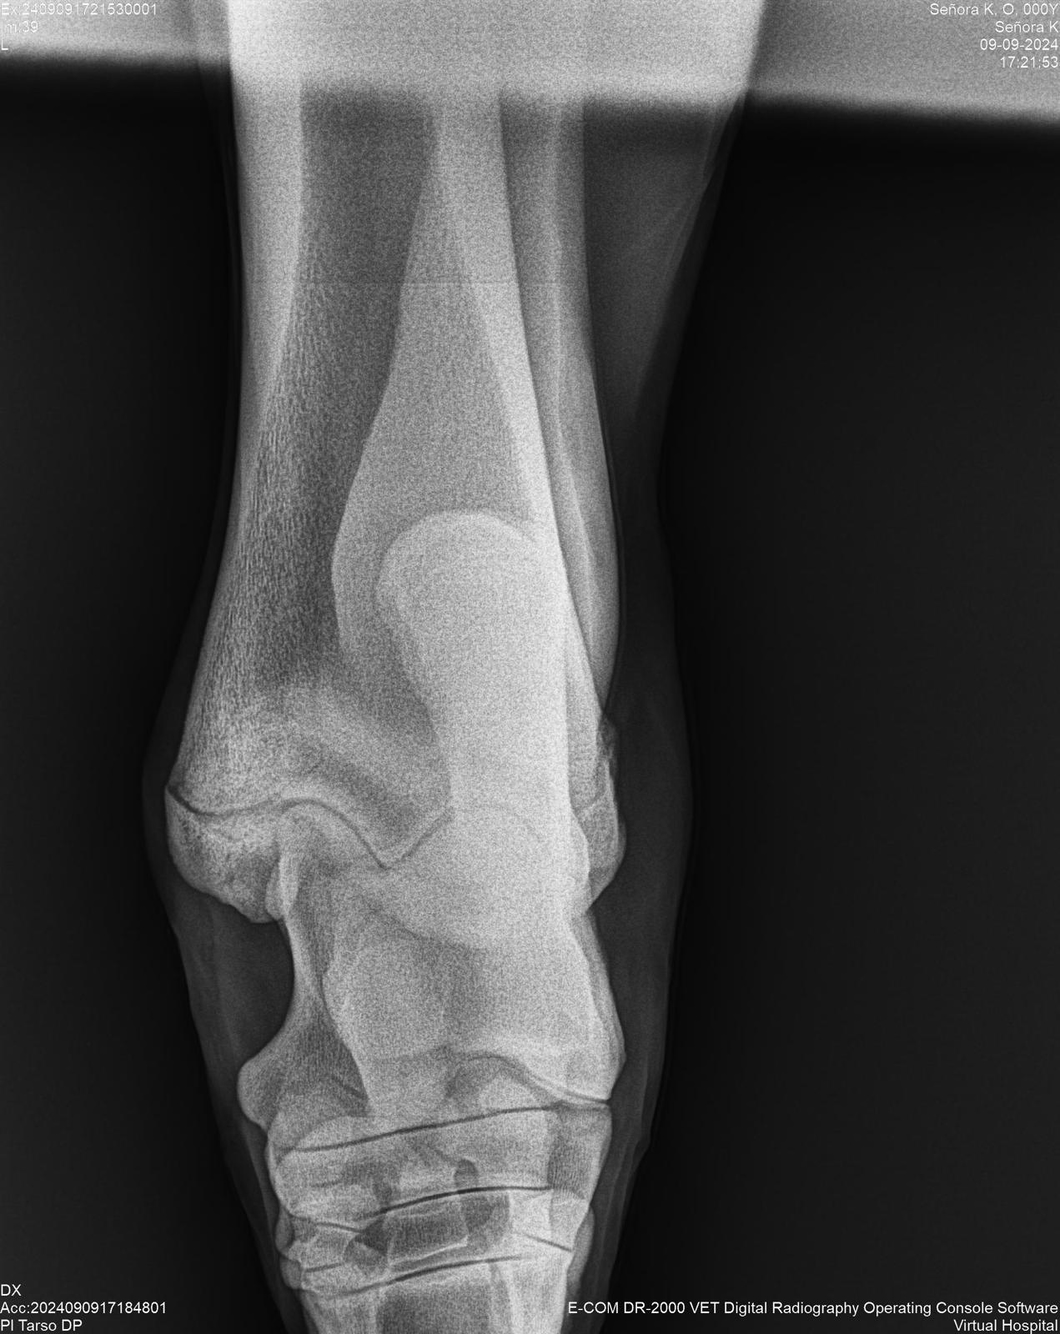

LOTE 44, SEÑORA K

Identificador: #291147-

Generacion 2022